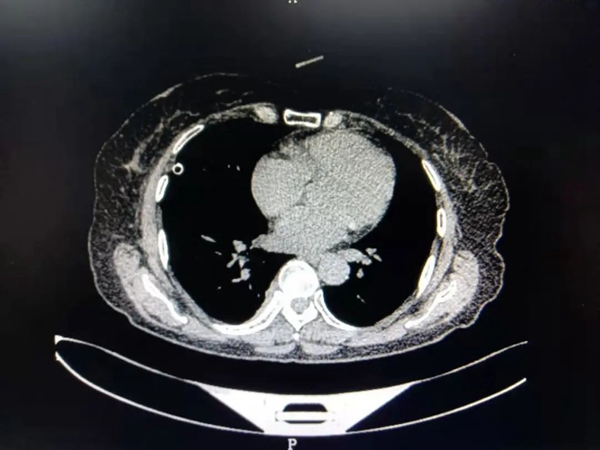

患者陈女士,59岁,因右侧胸背部疼痛半个月来我院就诊,经检查,胸部Ct结果显示:T8椎体旁紧贴胸膜处占位病变,且气管有先天畸形改变。陈女士既往有冠心病、高血压病和甲亢病史,家庭贫困。考虑其家庭状况,经充分术前评估,主管医生葛庆升详细告知陈女士病情及诊疗方案后,陈女士及其家属反复思量要求在家乡医院进行手术治疗。在郑州大学第二附属医院苏彦河教授的技术指导下,胸外科团队制定了周密的诊疗方案,因无法为陈女士完成单肺呼吸麻醉,经麻醉科会诊后,决定对其施行人工气胸胸右侧胸腔镜下纵膈肿瘤切除术,人工制造气胸,在纵膈中自下向上极度精准的操作,切除肿瘤。手术过程十分顺利,术中几乎无出血,术后患者恢复良好,现已康复出院。

![]() ![]() (术前CT) | ||